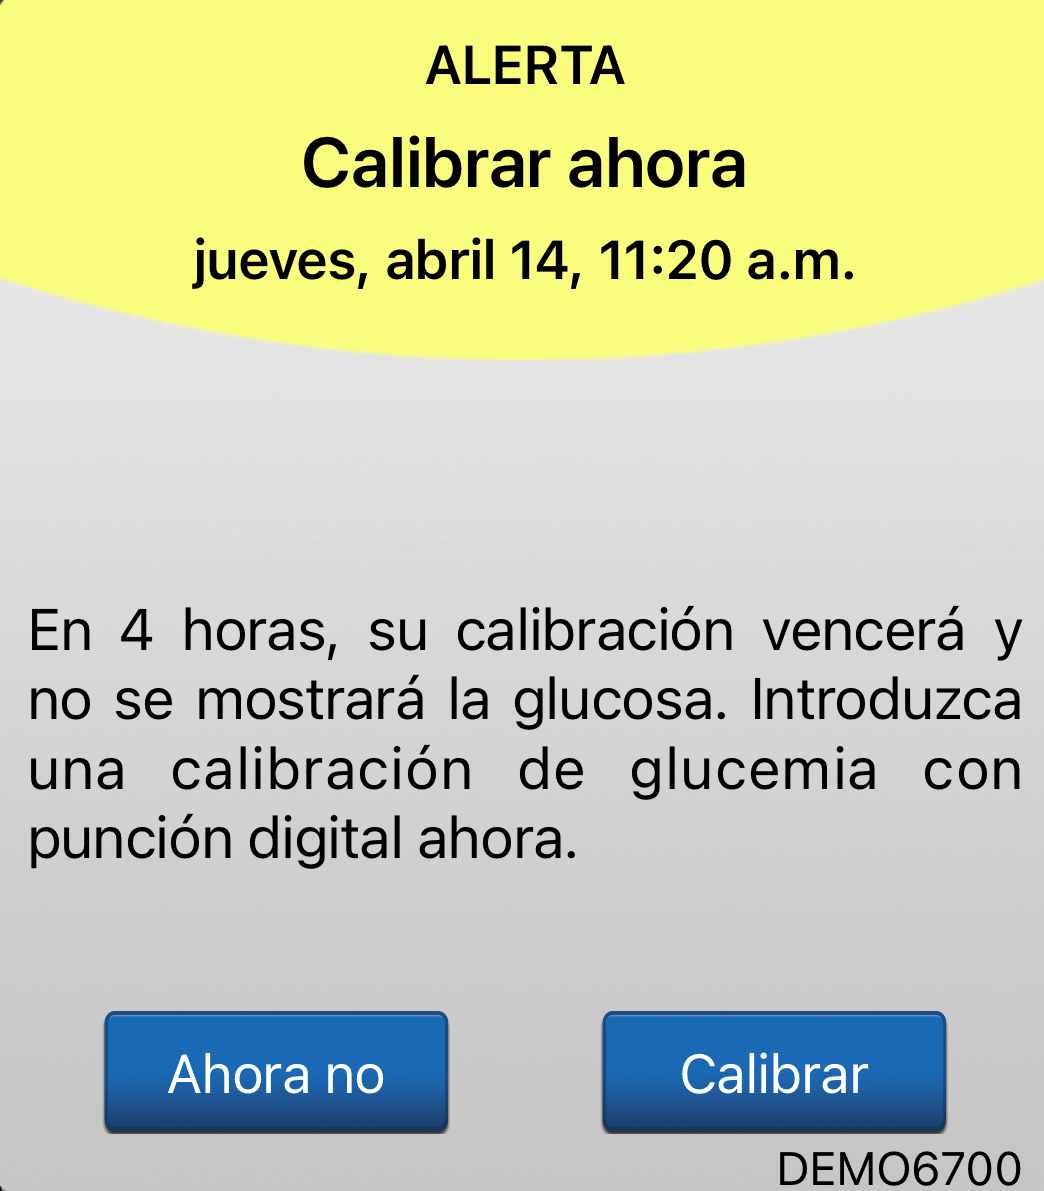

Otra alerta distinta es la alerta Calibrar ahora.

ALERTA DE CALIBRAR AHORA

El sistema de MCG de larga duración Eversense® E3 mantiene la exactitud durante los primeros 21 días mediante dos calibraciones diarias.

Posteriormente, a partir del día 22,

el sistema detectará si necesita

1 o 2 calibraciones al día.

Le indicará con la alerta Calibrar ahora que es necesaria una calibración.

ALERTA DE CALIBRAR AHORA

Aquí mostramos cómo funcionan juntas las alertas y notificaciones de calibración.

Cuando reciba la alerta Calibrar ahora y responda introduciendo

el valor de glucosa en sangre mediante punción capilar, recibirá una de estas dos notificaciones

si hay una actualización en

el momento de la próxima calibración.

ALERTAS Y NOTIFICACIONES DE CALIBRACIÓN

Si recibe la notificación “Fase de 2 calibraciones diarias”, significa que hay que realizar 2 calibraciones al día. Y se le recordará que realice una calibración aproximadamente cada 12 horas.

ALERTAS Y NOTIFICACIONES DE CALIBRACIÓN

Si aparece la notificación Fase

de 1 calibración diaria, significa que solo se necesita una calibración al día. Por tanto, verá las alertas "Calibrar ahora" cada 24 horas.

ALERTAS Y NOTIFICACIONES DE CALIBRACIÓN

Tenga en cuenta que cuando reciba una alerta Calibrar ahora, tendrá un margen de 4 horas para efectuar la calibración y mantener el acceso ininterrumpido a sus datos de MCG.